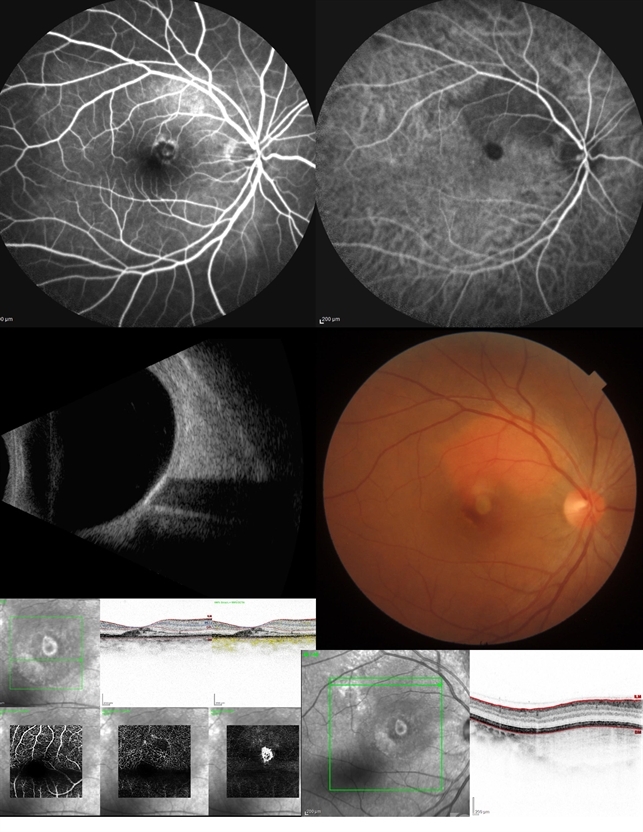

- Choroidal-tuberculoma, Tuberculosis, Choroidal Neovascularization

- Carlos Emiliano Rodríguez López. Instituto de Oftalmología FAP Conde de Valenciana, IAP.

- Imaging device

- Heidelberg Spectralis

- Multimodal image. 50-year-old female with choroidal neovascularization secondary to choroidal tuberculoma.